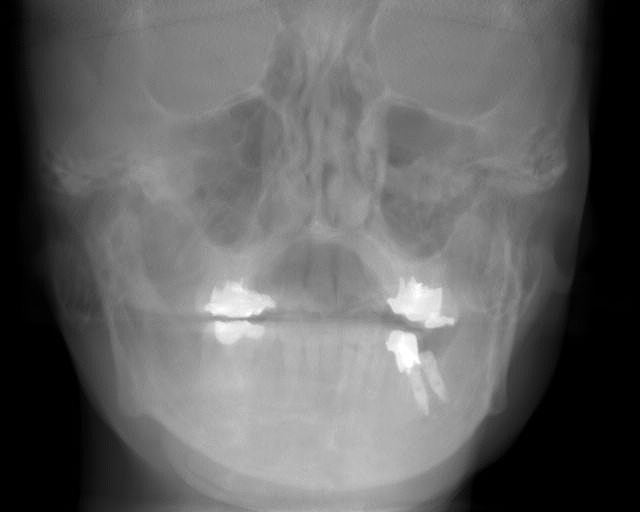

インプラント埋入後のパノラマになります

綺麗に入っているように見えますが、、、

左下の6番部になります

6番部になります

インプラントの埋入位置も制限され神経までの距離も近くなります

左下の7番部ではもっと埋入位置に制約が生じます

神経との距離も近くなります

インプラント自体を傾斜埋入せざるを得なくなります